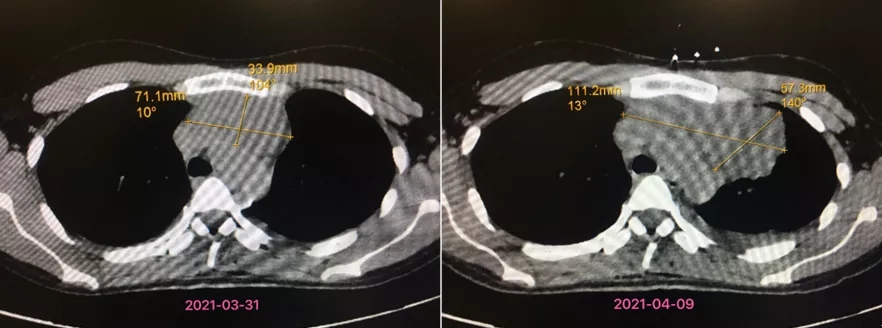

“一个多礼拜的时间里,患者的前纵隔肿物已经变大了很多。”心胸血管外科主任刘涛表示,经过前后两次CT结果的对比,患者的前纵隔肿物大小从71mm×34mm增长至111mm×57mm,增长迅速。

患者纵隔肿物增长迅速